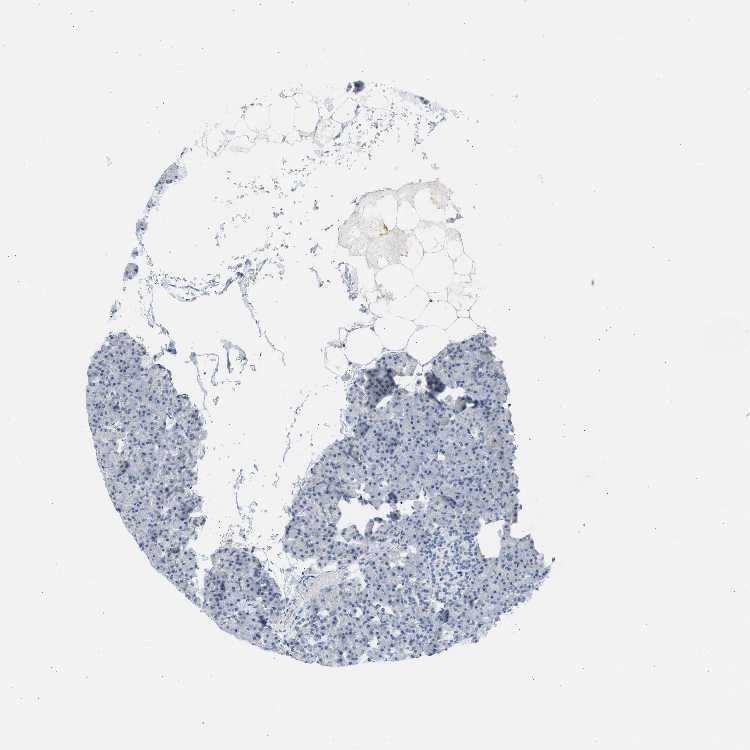

PANCREAS - Antibody stainingi

Antibody staining in the annotated cell types in the current human tissue is reported as not detected, low, medium, or high, based on conventional immunohistochemistry profiling in selected tissues. This score is based on the combination of the staining intensity and fraction of stained cells.

Each image is clickable and will lead to virtual microscopy that enables deeper exploration of all samples and also displays staining intensity scores, fraction scores and subcellular localization as well as patient and tissue information for each sample.

Antibody HPA001383Antibody CAB000043Antibody CAB020416Antibody CAB062555

Exocrine glandular cells MediumNot detectedNot detectedNot detected

Pancreatic endocrine cells LowNot detectedNot detectedNot detected